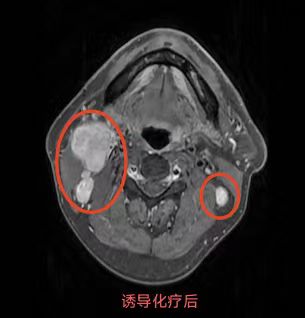

同步放化療(鼻咽癌伴頸部淋巴結(jié)轉(zhuǎn)移)